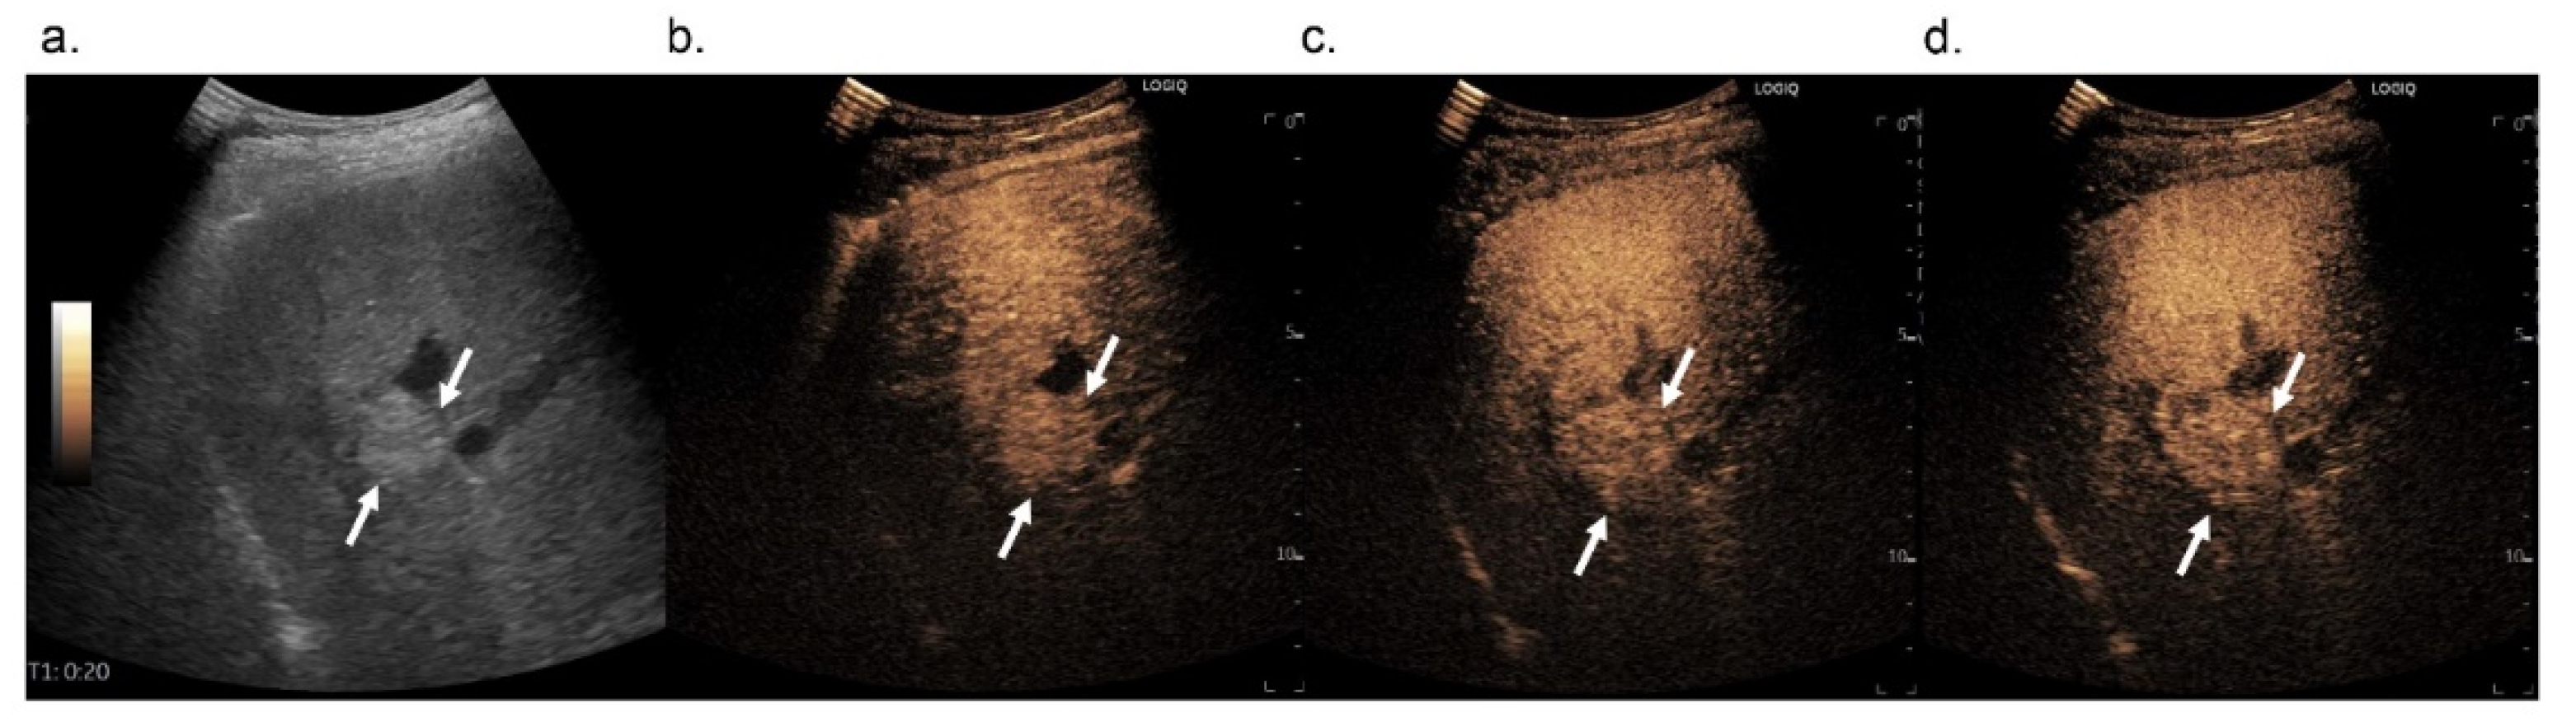

3.2.2. Washout

3.3. Diagnostic Performance of Hepatocellular Carcinoma Diagnosis Based on Both CEUS LI-RADS and Modified CEUS LI-RADS Using Qualitative Washout Results